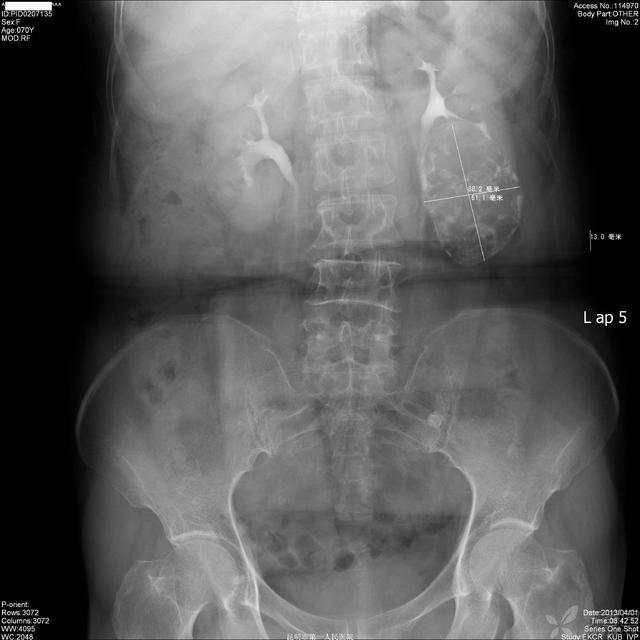

图1,KUB:

img

X线:左肾下极肿块,边界光滑,多发点片状钙化灶,左肾下肾盏受压移位、拉长、变形,肾盂输尿管上段未受侵犯。